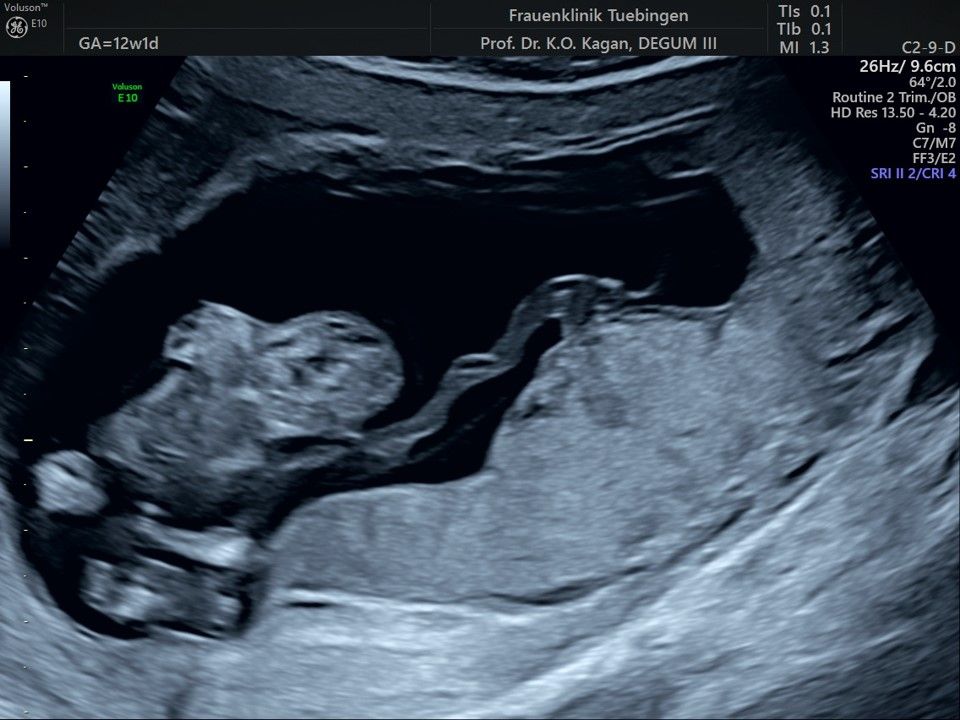

Im Rahmen des Ersttrimester-Screenings untersuchen wir die Organe des Feten mittels Ultraschall. Dabei machen wir auch gerne ein Bild für Sie.

Obwohl der Fet zu diesem Zeitpunkt erst zwischen 5 und 8cm groß ist, lassen sich bereits etwa die Hälfte aller schwerwiegenden Fehlbildungen erkennen bzw. ausschließen. Sollten wir eine Auffälligkeit sehen, werden wir mit Ihnen den Befund und das weitere Vorgehen ausführlich besprechen.

Fetale Anatomie